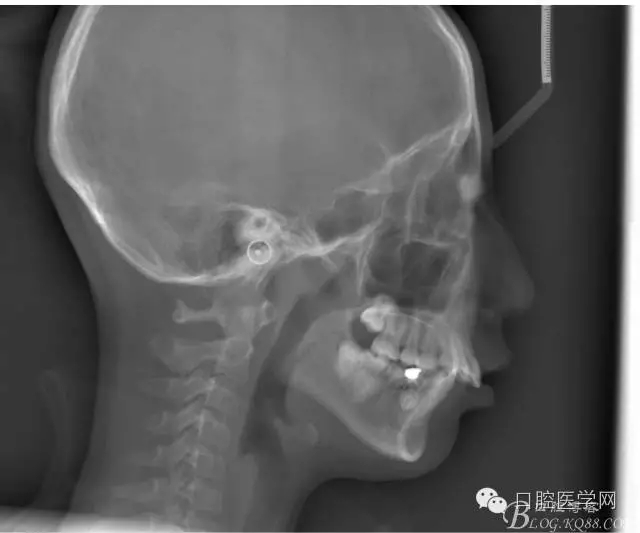

正畸查:替牙合。第一恒磨牙中性合。上牙弓尖圓型下牙弓方圓型。前牙覆合3度覆蓋7.5mm。下前牙咬到上舌側(cè)牙齦。上頜擁擠4.0mm,下頜擁擠

3.0mm。上頜稍前突下頜后縮,上下唇前突,上前牙覆蓋下唇,下唇外翻。面下三分之一過短,頦唇溝明顯,開唇露齒,頦饜窩明顯。顳下頜關(guān)節(jié)開閉口無彈響,無壓痛,開口型開口度正常。

正畸前后頭顱側(cè)位SN平面和S點(diǎn)重疊圖: